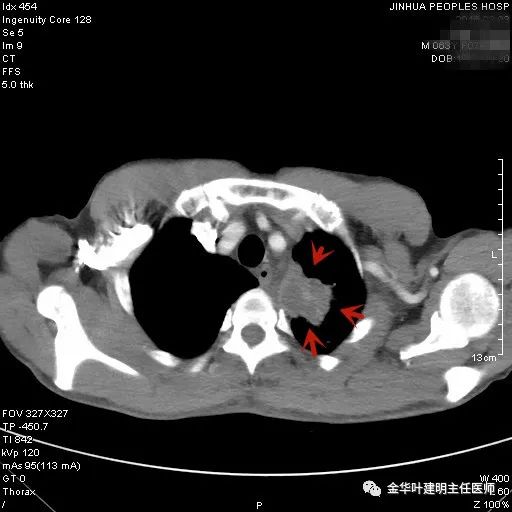

上图示鳞癌。病灶厚壁空洞,内壁凹凸不平,鳞癌可以乏收缩力,不一定有毛刺征或胸膜凹陷征。